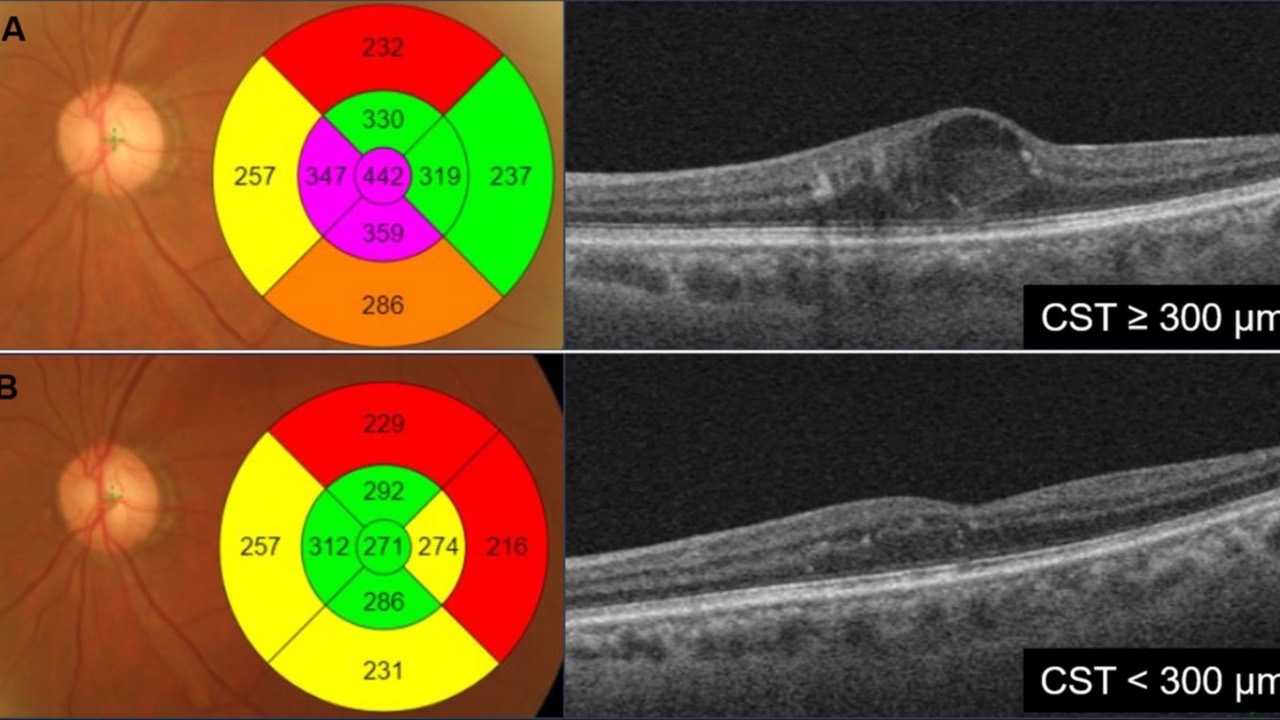

Anti-VEGF's & Glaucoma

The possible association between intravitreal anti-VEGF injections and the development of ocular hypertension or primary open-angle glaucoma has likely been a concern for all of us who follow these individuals in daily practice.

Anti-VEGF agents, while revoluti...